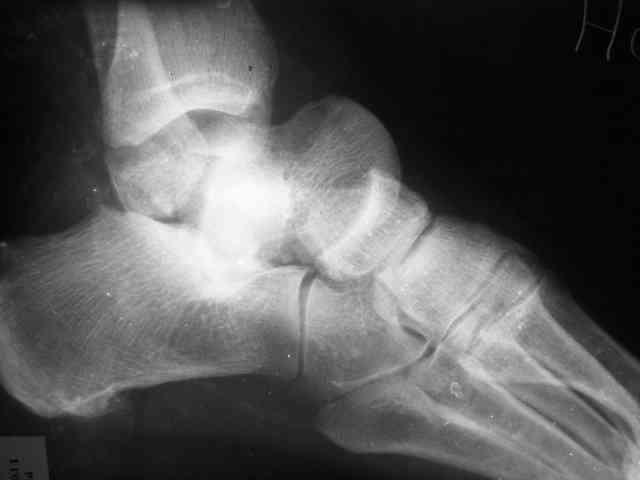

Уважаемый Александр! Как обещал представляю Р-граммы и операционные фото.

Опять надоедаю с вопросами:

Ваши (лично ваши) рекомендации - астрагалэктомия-аппаратный пяточно-большеберцовый артродез с одновременным удлинением голени - правильно?

Можно убрать таранную кость, и поместить в образовавшуюся полость либо бусы из цемента с антибиотиками, либо вылепленный прямо по форме тарана спейсер. Целесообразность этого будет определяться распространенностью гнойного процесса. Может быть, будет достаточно только удаления тарана.

Вместе с аваскулярным куском кости устранится субстрат. Надо опасаться не мягких тканей, а плохо кровоснабжаемых. Если после удаления тарана добиться контакта хорошо васкуляризованных пятки и больщшеберцовой, мягкие ткани не давить, чтобы некроза раны не было, то все должно зажить.